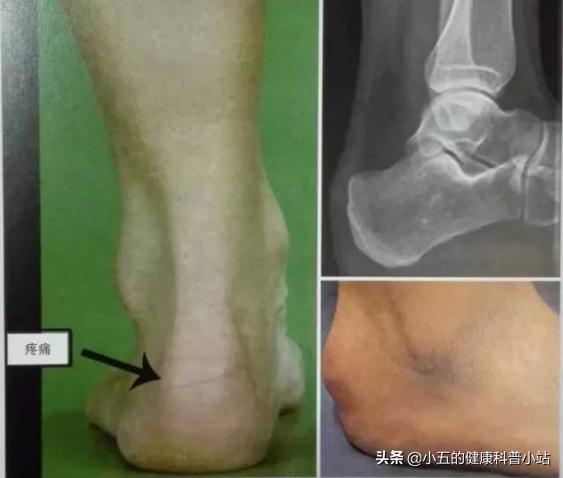

④跟骨骨刺

跟骨骨刺

跟骨骨刺是跟骨结节处向前延伸的骨赘,是长期的应力损伤造成的病理性增生。一般情况下跟骨骨刺病不会出现明显的临床症状,但当跟骨骨刺对周围腱膜、足跟脂肪垫形成潜在刺激,累积性刺激造成跟骨骨刺周围组织水肿增生增厚,进而刺激神经成为跟痛潜在致病因素。由跟骨骨刺引起的足跟痛症状常有以下发作特点: 跟骨下骨刺在早期形成阶段可引起疼痛,虽然此时骨刺很小,甚至X线检查也不能发现。严重者足跟底部顽固性疼痛,晨起或休息后开始,走动时症状明显。查体跟骨结节处压痛明显,患足足弓加深,结合X线检查可明确诊断 。